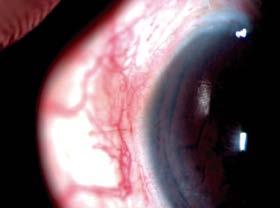

Presentación

En adultos, el glaucoma causa daño al nervio óptico; en niños, el daño se causa en prácticamente todas las estructuras del ojo. Los ojos jóvenes, sobre todo antes de los 3 años de edad, son muy elásticos así que una elevación de la presión intraocular causará daño estructural a todos los niveles. El ojo crece a mayor velocidad de lo que está preparado.

La expansión de los tejidos se manifiesta de las siguientes formas. En la córnea se producen roturas en la membrana de Descemet, conocidas como estrías de Haab, y también opacidades corneales. Esto causa lagrimeo excesivo, sensibilidad a la luz y blefarospasmo, típica triada de síntomas de glaucoma congénito. Además, el diámetro corneal y la longitud axial pueden aumentar significativamente, dando lugar al conocido ojo buftálmico. (Figura 1) El diámetro corneal de un recién nacido es de 9.5 a 10 mm. Un diámetro corneal de más de 10 mm en un recién nacido o más de 12 mm en un menor de 1 año de edad es sospechoso de glaucoma.

Dra. Elena Bitrian

También se observa adelgazamiento escleral, alargamiento de la longitud axial y miopía. El alargamiento de las zónulas puede producir su rotura y la consiguiente pérdida de soporte del cristalino, dando lugar a ectopia lentis. El iris puede presentar hipoplasia y adelgazamiento de tejido. A nivel del nervio óptico, se evidencia un aumento de la excavación que, a diferencia de lo observado en adultos, puede ser reversible tras la reducción de la presión intraocular, debido a la mayor flexibilidad de la lámina cribosa en la infancia.

Figura1. El incremento de presión intraocular en ojos pediátricos puede producir una expansión de los tejidos intraoculares (a), con estrías de Haab (b) y excavación del nervio óptico.